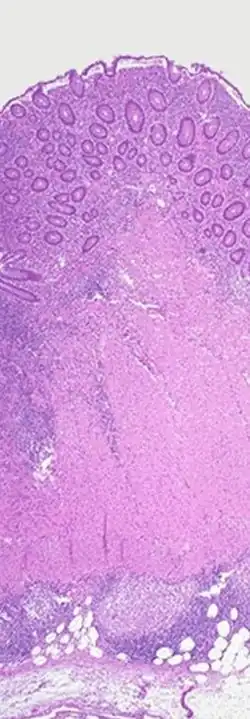

Charakterystyczne dla przebiegu choroby jest zajęcie całej grubości ściany narządu oraz możliwość występowania w całym przewodzie pokarmowym, podczas gdy we wrzodziejącym zapaleniu jelita grubego zajęte są tylko błona śluzowa i podśluzowa jelita grubego). Zmiany mają charakter ogniskowy (ang. skip lesions), w przeciwieństwie do wrzodziejącego zapalenia jelita grubego, w którym występują zmiany ciągłe.

Obraz histopatologiczny wykazuje występowanie ziarniniaków nabłonkowatokomórkowych bez cech serowacenia.